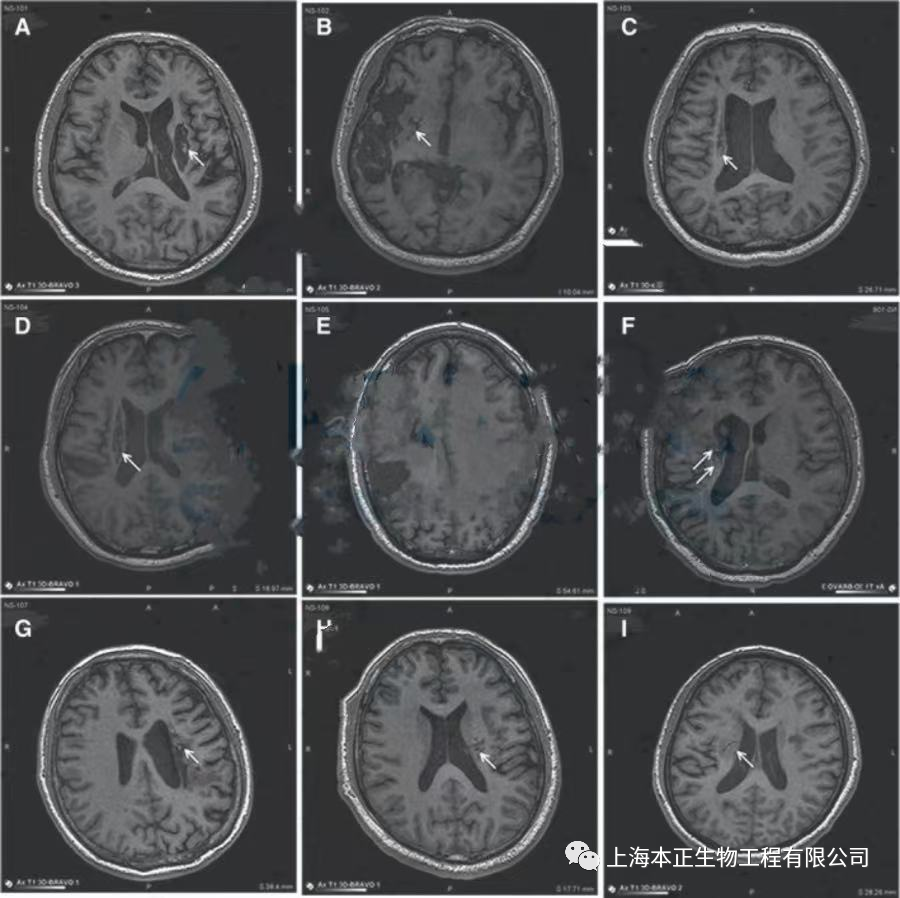

2019年,合作医院一研究团队在《Stem Cells Translational Medicine》发表了一篇关于神经干细胞脑内治疗缺血性中风瘫痪的研究。此项研究中使用的是NSI-566 原代贴壁神经干细胞系,来源于一位人类胎儿脐带,且未进行基因修饰。在此研究中所有9名受试者均患有慢性中风,分为三组(每组 n = 3)接受一次脑内注射不同密度干细胞。经磁共振成像 (MRI) 验证,所有 9 名患者的脑部都有新神经组织形成来填充空腔。如下图所示,箭头所指位置为梗塞腔。同时,所有患者在接受干细胞治疗后经过量表评分发现其运动功能均得到一定改善。因此可以表明,干细胞在治疗偏瘫性脑卒中具有一定改善效果。